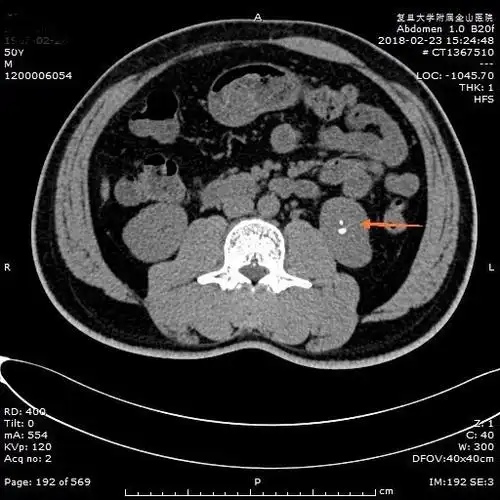

双能量ct可将尿酸结石和其他类型的肾结石区分开来:后处理结果会显示

泌尿系统结石之肾结石ct表现